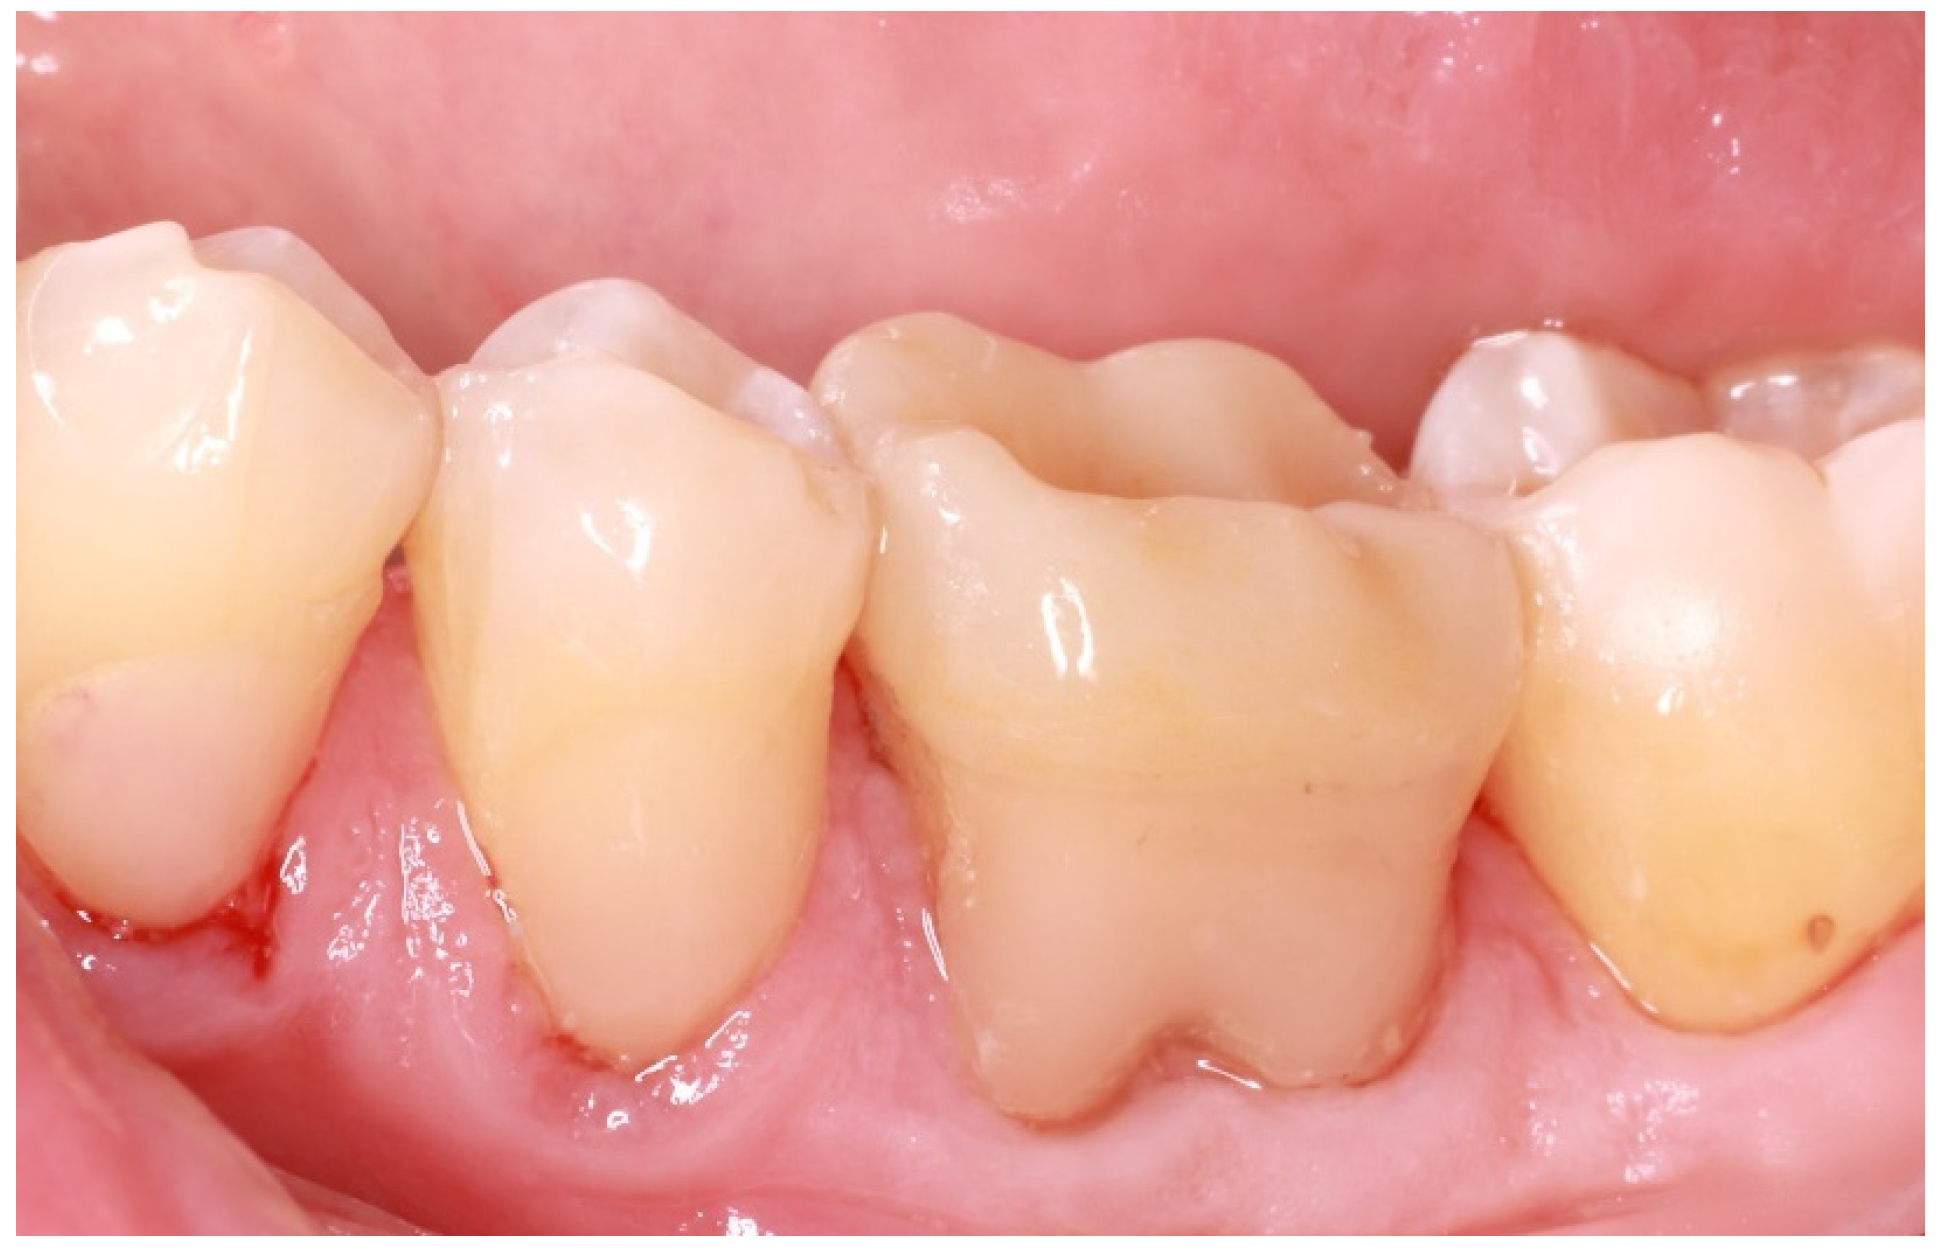

First, existing restorations and decayed tissue were removed. Given that the tooth was restorable, a provisional restoration was placed in order to prevent microleakage and the patient was referred for an endodontic reintervention as the existing root canal treatment was not satisfactory. Enamel presence at a percentage higher than 80% of the tooth circumference substantiated the choice of an endocrown restoration (Figure 2). This type of prosthesis demands the presence of healthy enamel for the adhesive procedures to be more effective [10]. This condition is so crucial that many reports have placed a lack of cervical enamel among the contraindications for endocrown restorations [11].

Figure 2. Adequate enamel presence after removal of previous restorations.